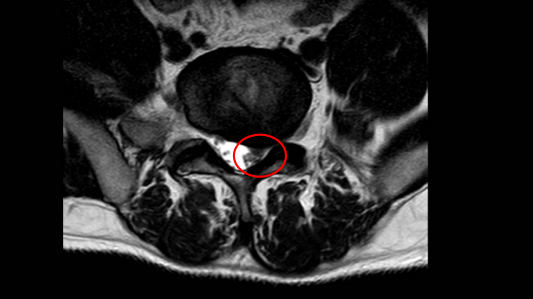

彭先生,34岁,1个月前开始出现左侧腰腿痛,先于当地医院诊治,经保守治疗之后症状并无缓解,就来到了深圳市人民医院脊柱外科就诊。体格检查发现:椎旁肌肉紧张痉挛,腰背部压痛;左下肢肌力、感觉减退,左侧直腿抬高试验阳性。核磁共振检查结果如下:

根据彭先生的症状、体征和影像学检查,我们给彭先生进行了经皮椎间孔镜下L5/S1椎间盘髓核摘除手术,很快,彭先生就顺利出院了!